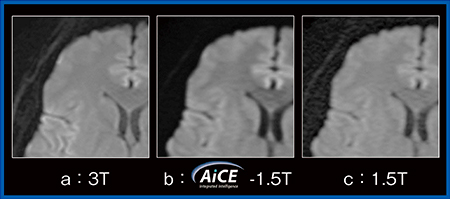

同一症例について,3Tと1.5Tの両方で脳のT2強調画像,FLAIR画像,拡散強調画像を撮像し,1.5Tの画像にはAiCEを適用したところ,3Tの画像と同等の画質が得られた。なかでも拡散強調画像では,3Tの画像(図1 a)にはairに起因する磁化率アーチファクトが目立つが,1.5Tの画像(図1 c)では目立たず,さらにAiCEを適用することで3Tと同等の画質となっている(図1 b)。SNRによる定量的評価および視覚評価においても,AiCEを適用した1.5Tの画像は3Tと同等の画質が得られるとの結果であった。

図1 頭部の拡散強調画像における3T画像とAiCEを適用した1.5T画像の比較

(画像ご提供:国際医療福祉大学・田島 拓先生)